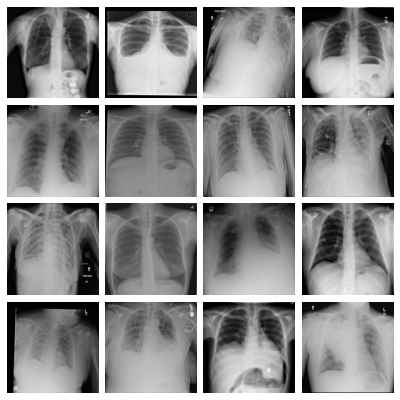

- cxr, Chest X-ray Multi-disease:

Dataset of frontal-view X-ray chest images, derived from the ChestX-ray14 dataset [wang_chestx-ray8_2017]. The 112,120 original images were resized to pixels using bi-cubic interpolation (no images were up-scaled); the 519 images that were originally in RGBA format were converted to grayscale. We provide a multi-label thorax disease classification task with 14 labels adopted without modifications from the source dataset. We additionally provide a binary classification task of the patient sex derived from the labels present in the original data.

- pneumonia, Pediatric Pneumonia:

Dataset of pediatric chest X-ray images labeled for pneumonia classification, derived from [kermany_identifying_2018]. The 5,856 original images were zero-padded to a square shape and resized to pixels using bi-cubic interpolation (some images were up-scaled); the 283 images that were originally in RGB format were converted to grayscale. From the original annotations, we derived a binary classification task for pneumonia presence as well as a multi-class task differentiating between normal images, bacterial pneumonia and viral pneumonia.